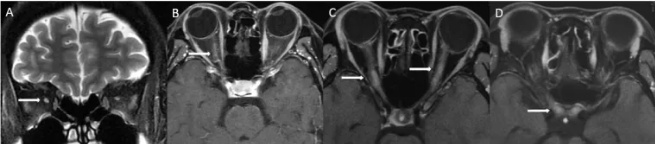

NMOSD患者MRI检查显示视神经病变(箭头所示)A:单侧ON;B:急性期视神经强化;C:双侧视神经炎,病变节段>1/2;D:病变累及视交叉